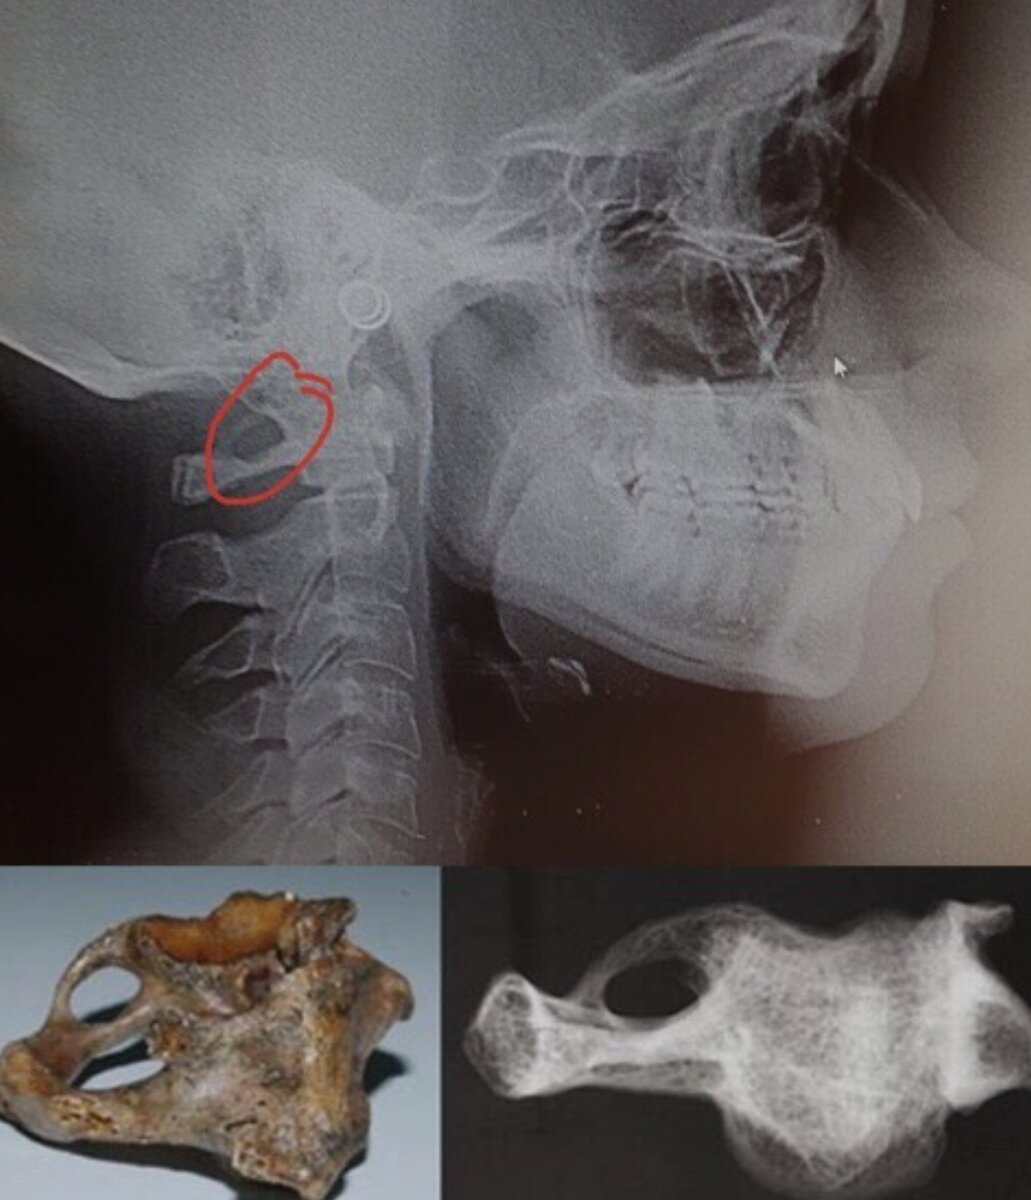

Аномалия Киммерли — это специфическое костное кольцо, которое окружает позвоночную артерию, проходящую через первый шейный позвонок. Оно может быть полным или неполным.

Выявить аномалию Киммерли несложно: она отчётливо видна на боковых рентгенограммах шейного отдела позвоночника. На первом шейном позвонке можно увидеть полную или неполную костную перемычку. Кроме того, степень толщины мостика и величина образованного отверстия могут сильно различаться.